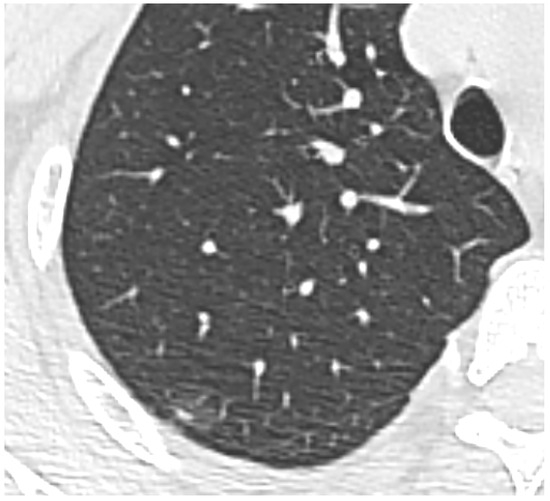

- Developments in low-dose CT screening;

- low-dose CT screening

- lung nodules